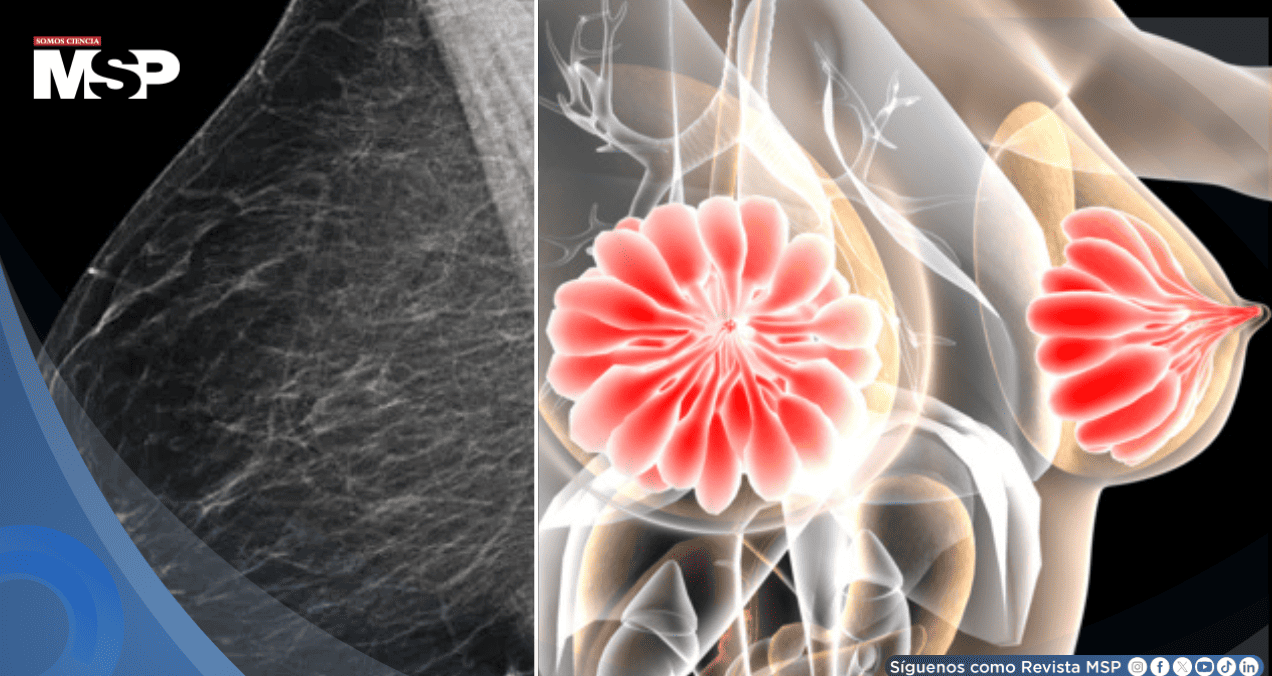

La densidad mamaria se refiere a la proporción de tejido fibroso y glandular en comparación con el tejido graso de las mamas. Es un factor importante porque las mamas densas, que aparecen blancas en la mamografía, pueden hacer que sea más difícil detectar el cáncer, que también se ve blanco.

"La densidad mamaria es una característica donde un mayor porcentaje del seno está constituido por tejido fibroglandular", explica el Dr. Juan Carlos Velázquez, la Clínica del Country y la Clínica La Colina. El problema es doble: en una mamografía, tanto el tejido denso como un posible tumor aparecen de color blanco, creando un efecto visual que puede ocultar lesiones cancerosas.